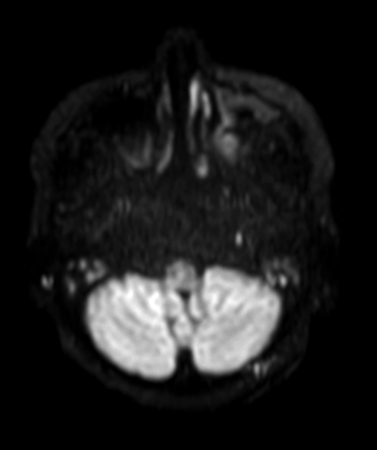

Axial DWI TSE (b1000)